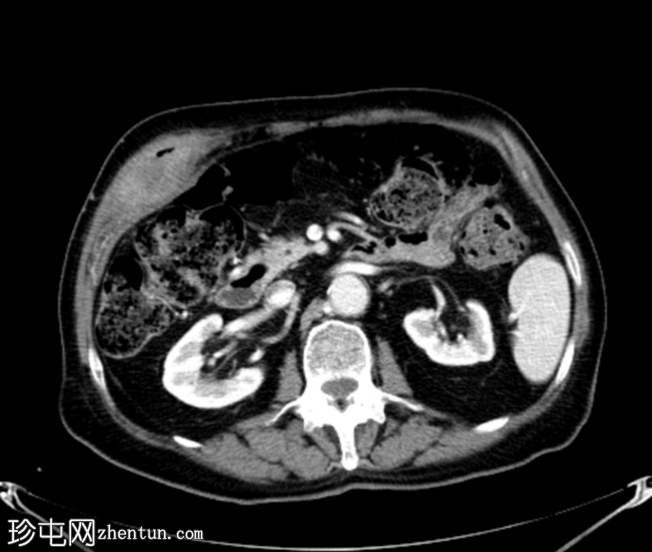

轴位增强扫描

动脉期

胆囊底部可见一枚较大的(3厘米)高密度结石,胆囊壁增厚并强化,主要位于胆囊底部。胆囊壁可见一小穿孔,感染扩散至胆囊外,并在肝下区可见气体腔。感染进一步扩散至腹壁肌肉,腹壁肌肉内可见脓肿,边缘强化明显,囊性坏死中心,腔内可见气体腔。十二指肠第一段与炎症胆囊粘连。

检查结果提示急性胆囊炎合并腹壁脓肿。